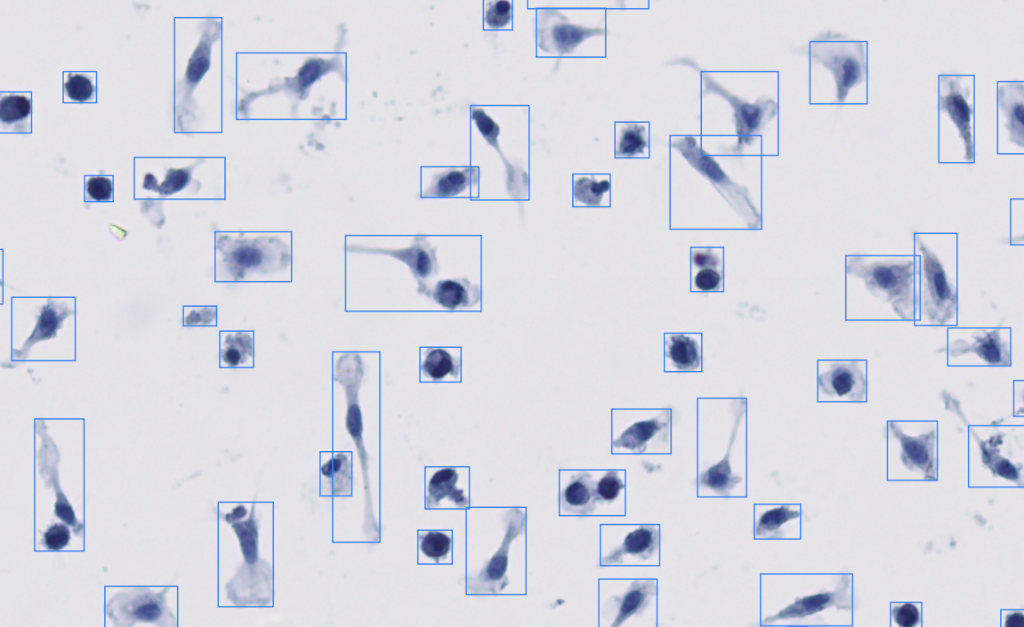

AI-driven cell detection, segmentation and quantification

AI-powered detection, segmentation, and counting with scientific precision.